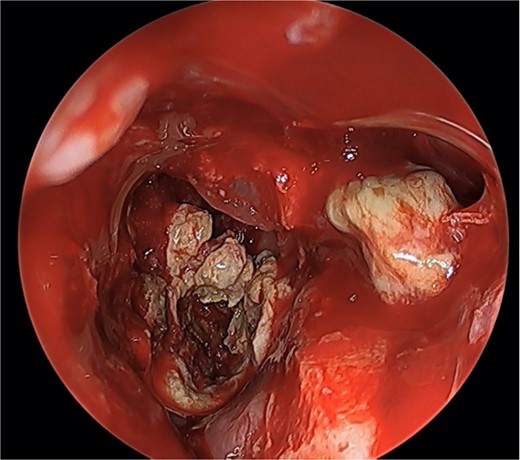

We present a case of a 52-year-old female, not known to have any chronic disease, who presented to our institution’s otorhinolaryngology clinic with a complaint of headache, facial pain, and PND for 6 months. Endonasal endoscopic examination was unremarkable. A paranasal sinus CT was requested to aid the diagnosis, which showed two simultaneous opacities occupying the left maxillary and right sphenoid sinuses, respectively (Fig. 1A and B). The opacified lesions were associated with calcifications, metallic shadowing, and bony thickening of the sinus wall. According to the history and radiological imaging findings, a diagnosis of a fungal ball occupying both the maxillary and sphenoid sinuses was achieved, and a functional endoscopic sinus surgery (FESS) with left wide maxillary antrostomy removal of the thick fungal debris occupying the left maxillary sinus (Fig. 2) was decided to be performed. In addition, a wide endoscopic sphenoidotomy was performed, and the sphenoid sinus was full of fungal debris (Fig. 3), which was cleaned thoroughly. The patient had an uneventful post-operative course.

Post-operative endoscopic view post sphenoidectomy and maxillary antrostomy.